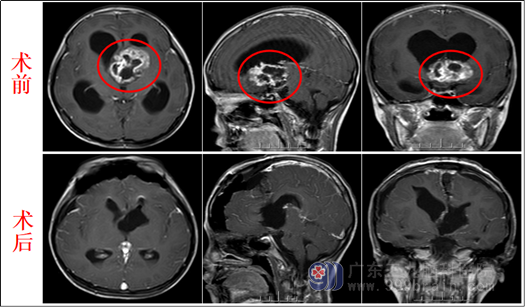

影像检查:

术前MR与术后MR对比图

幸运的是,小芳的家人在医院找到了经验丰富的神经外科医生。在充分了解病情后并完善术前准备后,欧阳辉教授带领外十科团队决定采用直接手术的方式为小芳进行治疗。头颅MR示:1.鞍上区至透明隔区占位性病变,考虑毛细胞星形细胞瘤可能性大;2.幕上梗阻性脑积水并室周间质水肿。患儿术前已经非常虚弱,脑积水严重,已有脑疝前期表现。 手术指征明确。9月27日外十科在全麻下为患儿行经右侧前纵裂-胼胝体-侧脑室入路行鞍上区-透明隔占位切除术,肿瘤位置深,手术难度大。医生如履薄冰、如临深渊,在高清显微镜下,小心翼翼地切除肿瘤,保护好大脑内静脉等重要血管及下丘脑等重要神经结构,最终将肿瘤全切除。术后病理为:毛细胞粘液性星形细胞瘤可能性大。术后小芳很快清醒,解除了危险,现小芳恢复良好,已转肿瘤科行后续治疗。